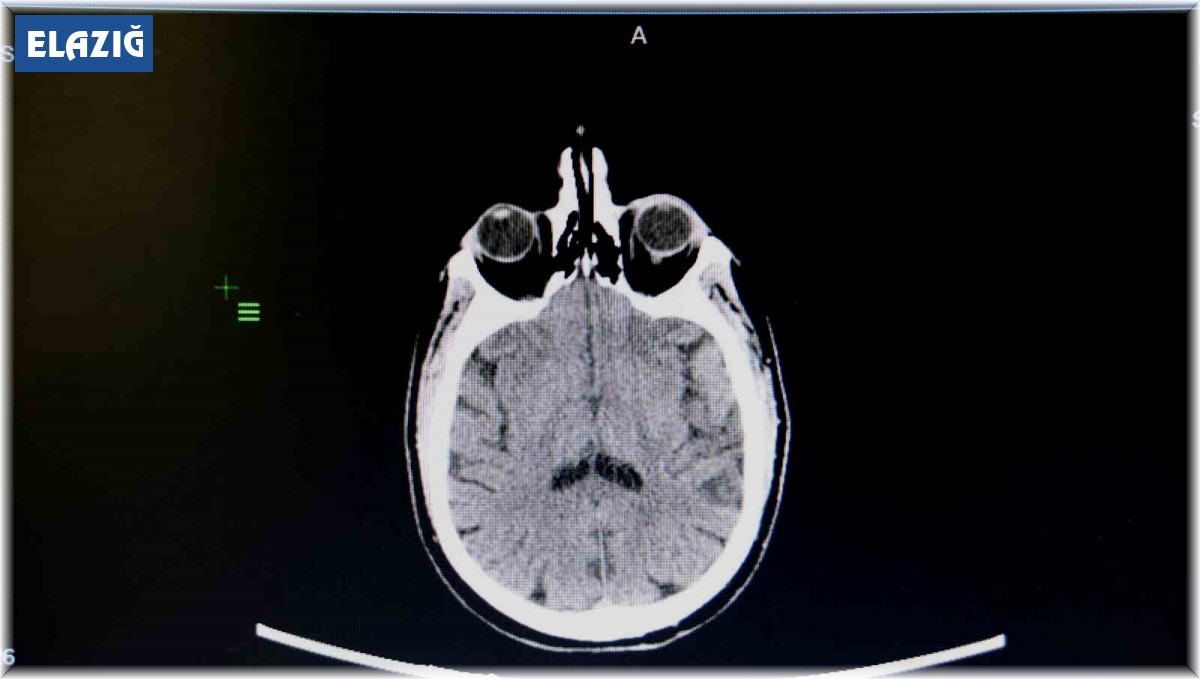

Elazığ - Elazığ Fethi Sekin Şehir Hastanesinde görevli Kulak Burun Boğaz (KBB) Uzmanı Prof. Dr. Öner Sakallıoğlu, işitme kaybı hakkında açıklamalarda bulunarak vatandaşlara tavsiyelerde bulundu. İşitme kaybının toplumdaki her yaşta görülebileceğini ve sıklıkla rastlanabileceğini aktaran Prof. Dr. Öner Sakallıoğlu, "İşitme kaybı her yaşta görülebildiği için bulunduğu dönem itibariyle gerek bir engel teşkil etmesi gerekse de iletişimi engellemesi ya da çocuklarda dil gelişmesi sorunlarına yol açması bakımından oldukça önem taşımaktadır. İşitme kaybı genelde hastaların işitmelerinin az olmasını ifade etmesiyle ortaya çıkar. Yeni doğan bebeklerde pek mümkün olmasa da onlarda yapılan çeşitli testlerde bu işitme kaybı ortaya çıkartılabilmektedir. Tedavi süreçleri genel olarak yaşla ilgili sebeplere bağlı olarak değişebilmektedir. Çünkü oldukça farklı sebepleri olabilir. Özellikle çocukluk çağı başta olmak üzere erişkin çağ ve daha ileri yaş olan yaşlılık döneminde çeşitli yöntemlerle tanı ve tedavisi yapılabilmektedir. Halk arasında doğru olarak bilinen fakat tıp dilinde yanlış olanların belki de en önemlisi işitme kaybının tedavisinin olmayacağı yönünde bir görüş hakim. Fakat işitme kaybının çok büyük bir kısmı tedavi edilebilmektedir. Gerek ameliyat yöntemleriyle gerekse de tedavi yöntemleriyle işitme kayıplarının çok büyük bir kısmı tedavi edilebilmektedir. Özellikle kulak çöplerinin kullanımı çok doğru olmayabilir. Toplumda çoğu insan kulağını temizlemek amacıyla kulak çöpü ya da başka cisimler kullanmaktadır. Bunların sıkıntılara yol açma ihtimalleri oldukça yüksektir. Kulak salgısının azaltılmasına yol açarak kulağın kurumasına ve kaşıntıya yol açabilir. Onun haricinde kulakta yabancı cisimler oluşturabilir. Bunlar kulak zarı yırtılmasından tutalım da kulak kanalının çizilmesi ve dış kulak enfeksiyonlarının ortaya çıkması gibi sorunlara neden olabilir. Bunların tedavisi mümkün fakat kulak çöpü gibi yabancı cisimlerin kullanılmasını çok tavsiye etmemekteyim. Çoğu vatandaşta dış kulak kanalından sarımsı bir şekilde gelen sıvı akıntısı olmaktadır. Bunlar kulağımızın normal bir salgısıdır. Bunların illa temizlenmesi gerekmiyor. Daha önce bahsettiğimiz gibi bunların fazlaca temizlenmesi dış kulak kanalında travmalara belki de istemediğimiz enfeksiyonlara yol açabilmektedir. Bu yüzden sakıncası bulunmaktadır" dedi.